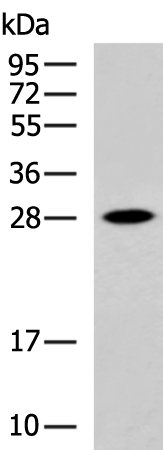

分类: 科研抗体货号: P10675别名: NGFB; HSAN5; Beta-NGF应用: WB,IHC反应种属: Human, Mouse, Rat